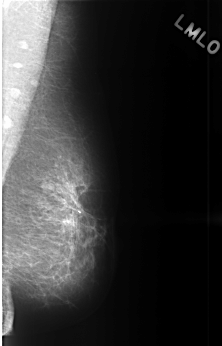

C_0450_1.LEFT_MLO

LEFT_MLO LINES 4496 PIXELS_PER_LINE 2880 BITS_PER_PIXEL 12 RESOLUTION 50 NON_OVERLAY